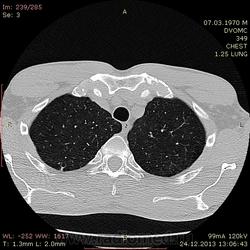

43 года. На флюшке нашли очаг на верхушке. Жалоб нет. Архива нет.

Узелок сязанный с плеврой. Или полость мелкая с толстыми стенками. Наверное, стоит склоняться к туберкулёзу. Хотелось узнать Ваше мнение, коллеги.

Да, действительно, малая полость распада есть. Вероятнее всего, туб этиологии. В настоящий момент, скорее всго, в фазе уплотнения. Желательно обследовать на активность туб. процесса, да оставить на динамическое наблюдение.

Андрей Юрьевич

Посчитала бы за старые очаги, как последствие перенесенного процесса. На фоне парасептальной и центролобулярной эмфиземы в верхушках есть несколько таких очагов, кавитация кажущаяся, из-за близости участка эмфиземы (ИМХО). Рекомендовала бы туб.пробы и КТ-контроль через пару месяцев с записью: на данный момент признаков активности процесса нет.

В саггитале полостюшка смотрится несколько интересно. Создается впечатление буллезной полости с участком уплотненной и частично кальцинированной стенкой. А если исходить из этого, то и дренирующего бронха не будет. Очаги приведенные коллегой ЛГ очень плотные даже на взгляд. Т.е. ТБ если и был, то эта полость не его